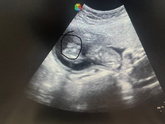

Кто сдавал ? Что будет если этот порошок ( глюкоза ) в воде не полностью растворится ? Если я выпью его на ответы это влияет ? Мне мед сестры сказали что нет , а в инете пишут что полностью глюкоза должна растворится . ( сдаю впервые и не знаю как правильно … Читать далее